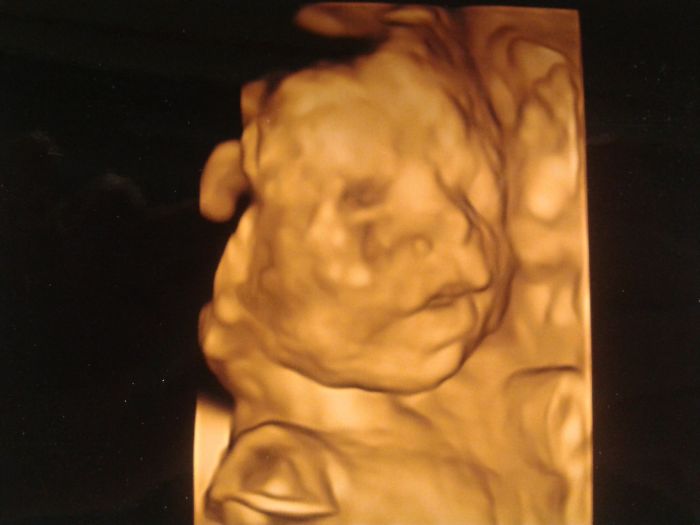

Holky, krásné fotečky. My máme jen z velkého UV z OL, ale pěknou, koukněte